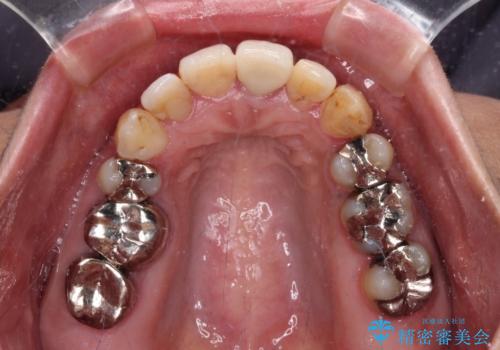

口元を引っ込めることができたため、口を閉じるときに力が入っていて皺のよっていた顎先も、スムーズに閉じられるようになったことで力がかからなくなりました。

変色して気になっていた前歯も、オールセラミッククラウンで自然な色合いにすることができました。

- 歯列全体が内側に倒れ込んでいることと、口元の突出感を気にして来院された患者様です。

上下ともに歯列が狭窄しており、前方に突出している状態でした。

歯が重なるような叢生も認められたため、上下左右の第一小臼歯4本を抜歯して、口元が引っ込むように治療を行うこととしました。